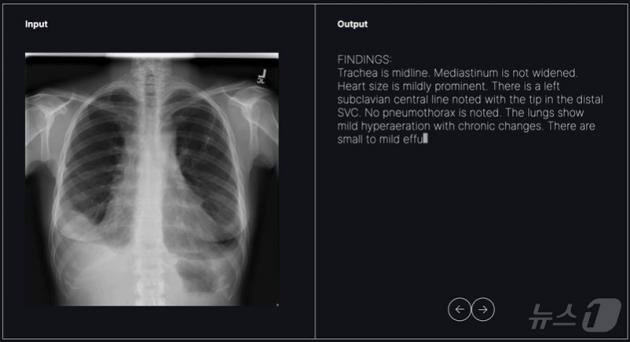

In 2025, Soombit AI received clinical trial approval from the Korean Ministry of Food and Drug Safety for its 'AI Read-CXR' software.

This tool analyzes chest X-rays and generates personalized diagnostic drafts for radiologists. If approved, it could become the first generative AI-based medical device in Korea.

- Trial Sites: Seoul National University Bundang Hospital, Inha University Hospital

- Trial Method: 9 radiologists evaluating over 1,000 chest X-rays

- Expected Approval Timeline: End of 2025